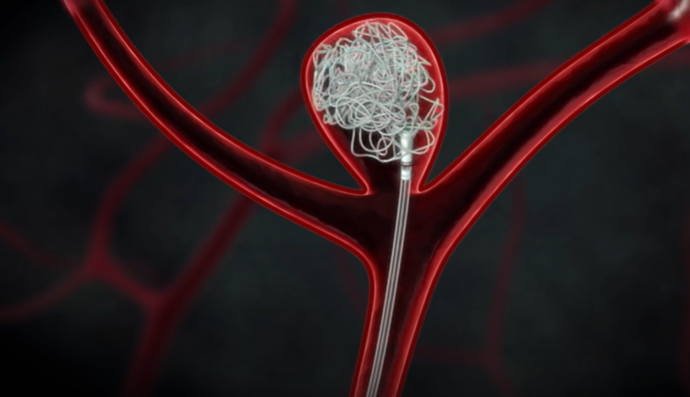

뇌동맥류 치료 : 클립 결찰술, 코일 색전술

혈관을 따라 와이어를 삽입한 뇌동맥류 안쪽 공간을 가느다란 코일로 채워주는 코일 색전술이 있다.

둘 다 뇌동맥류로 가는 혈류를 차단해 파열을 막아주는 효과가 있다.

대개 개두술, 경부 결찰술을 하는 뇌수술을 받으면 굉장히 위험하고 혈관 내 수술, 즉 코일 색전술은 안전하다 생각하는데 치료법의 결정은 동맥류의 모양에 큰 영향을 받는다. 경부(동맥류가 시작하는 목 부분)가 굉장히 좁고 동맥류 자체가 크면 코일 색전술을 하기 쉽다. 반대로 경부는 넓고 동맥류의 높이는 높지 않은데 위험한 위치에 있을 경우, 코일 색전술을 하면 동맥류가 불거진 부분에 코일일 지지할 곳이 없다. 이 경우 개두술을 하고 경부 결찰술을 시행하는 것이 훨씬 안전하고 효과적이다.